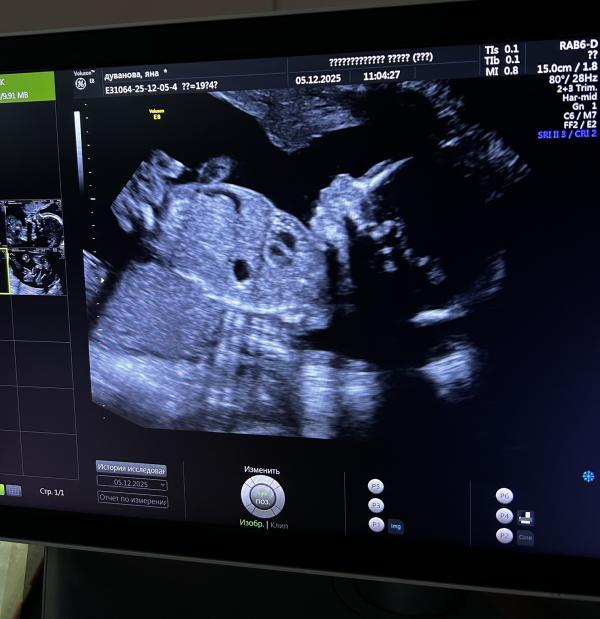

Когда на втором скрининге не успела задать вопрос о том, не отвалилась ли пиписька, как человек быстренько сунул её на весь экран.

Спасибо - пожалуйста😂

Это волшебное чувство, видеть этого человека на экране, и понимать что совсем скоро он будет на моих руках🙏🏼